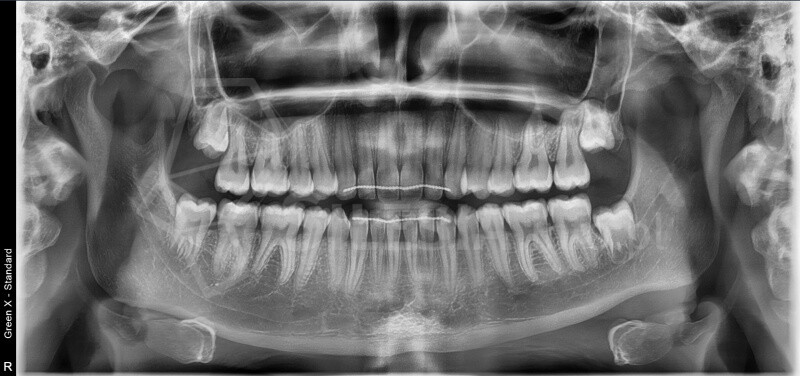

Zdjęcie panoramiczne (pantomogram) obejmuje całe uzębienie i szczęki, pokazując zmiany, których nie widać na zdjęciach punktowych RTG – takie jak torbiele, guzy, stany zapalne czy zwyrodnienia stawów.

To podstawowe badanie profilaktyczne, które warto wykonywać regularnie – przynajmniej raz na dwa lata.